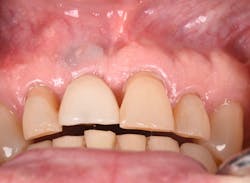

The Er:YAG laser has been more recently known for its ability to remove calculus from a titanium implant surface as well as detoxification (figures 17–21).9 Many authors have shown the laser’s use in combination with mechanical debridement to be superior when using a regenerative approach to treat peri-implant diseases (figures 22–26).10 A particular feature of this laser is the microexplosions that occur when the laser energy is absorbed by water. The volume of these explosions suddenly expand up to 1,000 times, covering more surface area of a titanium implant. It has been found that both contaminated debris and the contaminated oxide layer are removed as a result of these microexplosions.11

Figure 17: Patient presented with buccal vestibule swelling and complaining of pain. Swelling is visible and palpable with discoloration of the soft tissue.

Figure 18: Pre-op radiograph shows retrograde peri-implantitis possibly from previous periapical pathology.

Figure 19: Immediately after incisions and raising a full-thickness flap, suppuration was noted on the apex area of the implant.

A further interesting concept of the Er:YAG laser is the biostimulation phenomenon (photobiomodulation). This biologic effect can promote wound healing and reduce postsurgical inflammation.12 For this reason, the laser can be used for other clinical applications, such as treatment for aphthous ulcer removal, dentinal desensitization, and coagulation properties.

Figure 20: An osteotomy was done to access apical area of implant No. 8 utilizing the Er:YAG laser at 20 pps/70 mJ. The then-exposed area was irradiated using a combination of detoxification and biostimulation of the bone and implant to prepare the area to receive a bone graft.

Figure 21: After mechanical debridement and surface detoxification